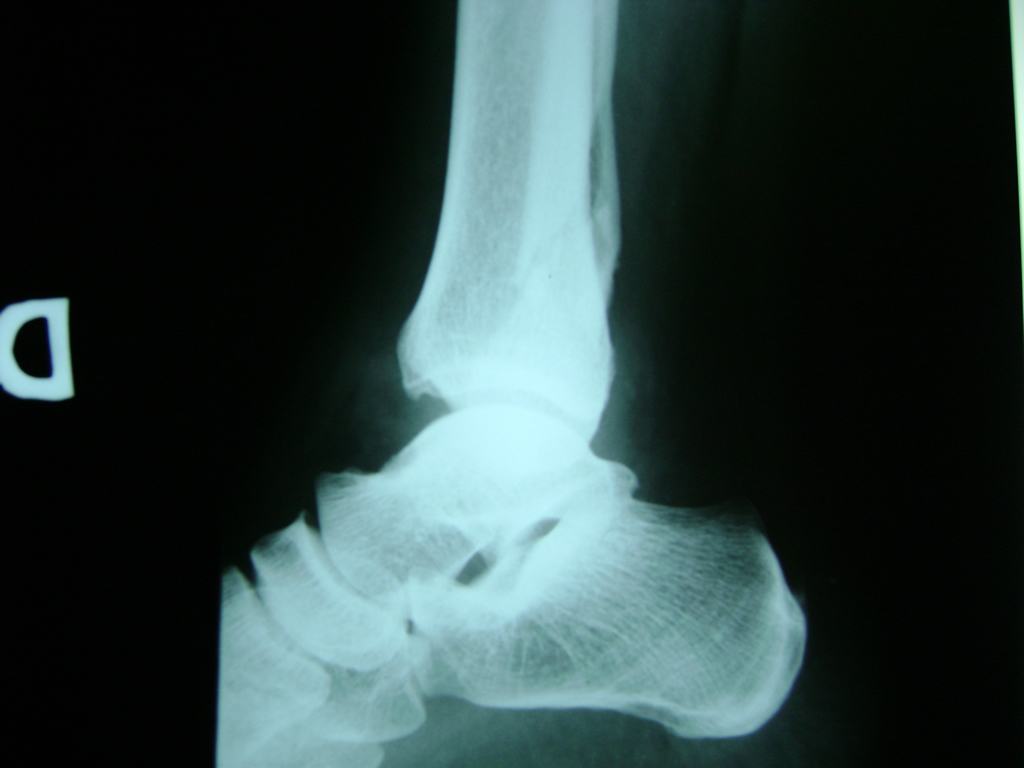

Una fractura de tobillo es la rotura de uno o más de los huesos del tobillo. Estas fracturas pueden ser:

- Parciales (el hueso está sólo parcialmente fisurado, no del todo).

- Completas (el hueso está perforado y está en 2 partes).

- Producirse en uno o ambos lados del tobillo.

Algunas fracturas de tobillo pueden requerir cirugía si:

- Los extremos de los huesos están desalineados entre sí (desplazados).

- La fractura se extiende hasta la articulación del tobillo (fractura intra-articular).

- Los tendones o ligamentos (tejidos que sujetan los músculos y los huesos entre sí) están rotos.